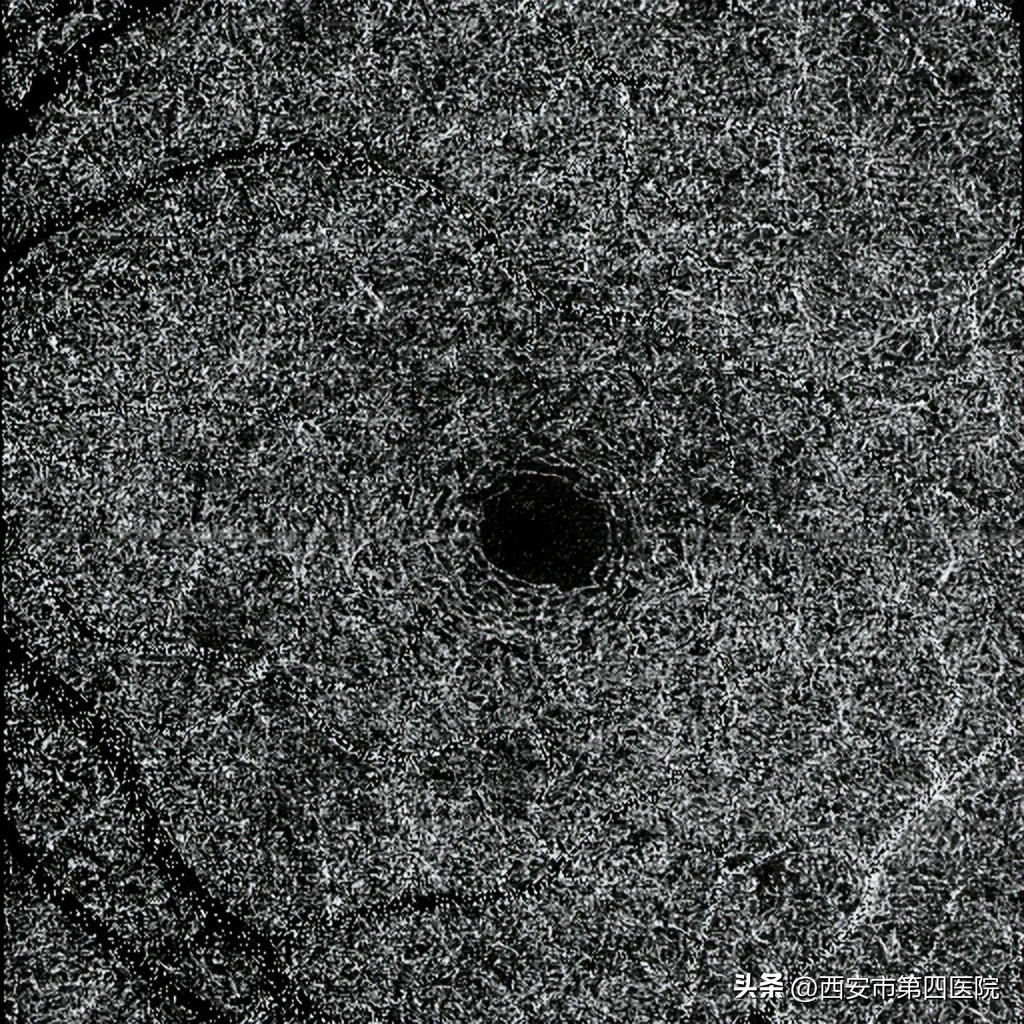

双眼红外(IR)成像:所示黄斑区可见“花瓣状”低反射信号,尖端指向中心凹)

双眼OCTA6*6mm检查: 黄斑周围深层毛细血管血流密度降低。

OCTA显示视网膜深层毛细血管网血流密度降低。